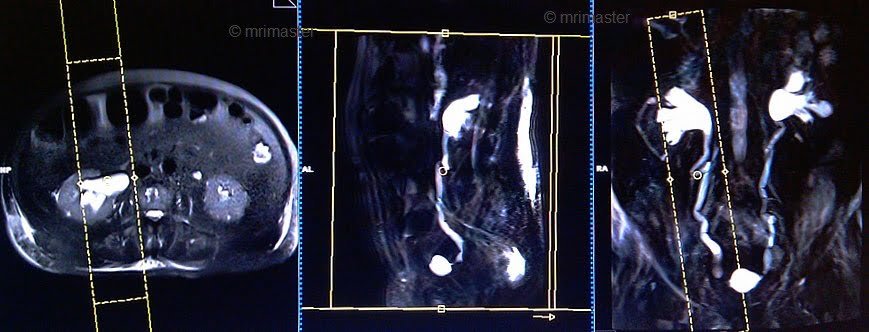

T1 flash FS/ vibe 3D DIXON coronal 2 mm arterial 25 seconds

Plan the coronal slices on the axial plane and angle the positioning block parallel to the right and left kidneys. Check the positioning block in the other two planes. An appropriate angle must be given in the sagittal plane (parallel to the L spine). Ensure that the slices are sufficient to cover the entire urinary system. Use phase oversampling and, in the case of 3D blocks, slice oversample to avoid wrap-around artifacts. The field of view (FOV) must be large enough to cover the kidneys and bladder. Instruct the patient to hold their breath while the images are being acquired. (In our department, we advise patients to take two breaths in and out before the “breath in and hold” instruction).

Parameters

TR 4-5 | TE 2 | FLIP 12 | NEX 1 | SLICE 2 MM | MATRIX 320X320 | FOV 350-400 | PHASE R>L | OVERSAMPLE 50% | IPAT OFF |

T1 flash FS/ vibe 3D DIXON coronal 2mm venous 50 seconds

Plan the coronal slices on the axial plane and angle the positioning block parallel to the right and left kidneys. Check the positioning block in the other two planes. An appropriate angle must be given in the sagittal plane (parallel to the L spine). Ensure that the slices are sufficient to cover the entire urinary system. Use phase oversampling and, in the case of 3D blocks, slice oversample to avoid wrap-around artifacts. The field of view (FOV) must be large enough to cover the kidneys and bladder. Instruct the patient to hold their breath while the images are being acquired.